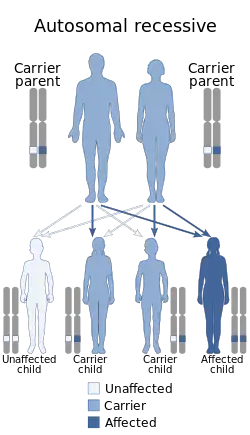

Genetics

Cerebral palsy is not commonly considered a genetic disease. About 2% of all CP cases are expected to be inherited, with glutamate decarboxylase-1 being one of the possible enzymes involved.[5] Most inherited cases are autosomal recessive.[5] However, the vast majority of CP cases are connected to brain damage during birth and in infancy. There is a small percentage of CP cases caused by brain damage that stemmed from the prenatal period, which is estimated to be less than 5% of CP cases overall.[78] Moreover, there is no one reason why some CP cases come from prenatal brain damage, and it is not known if those cases have a genetic basis.[78]

Cerebellar hypoplasia is sometimes genetic[79] and can cause ataxic cerebral palsy.[80]